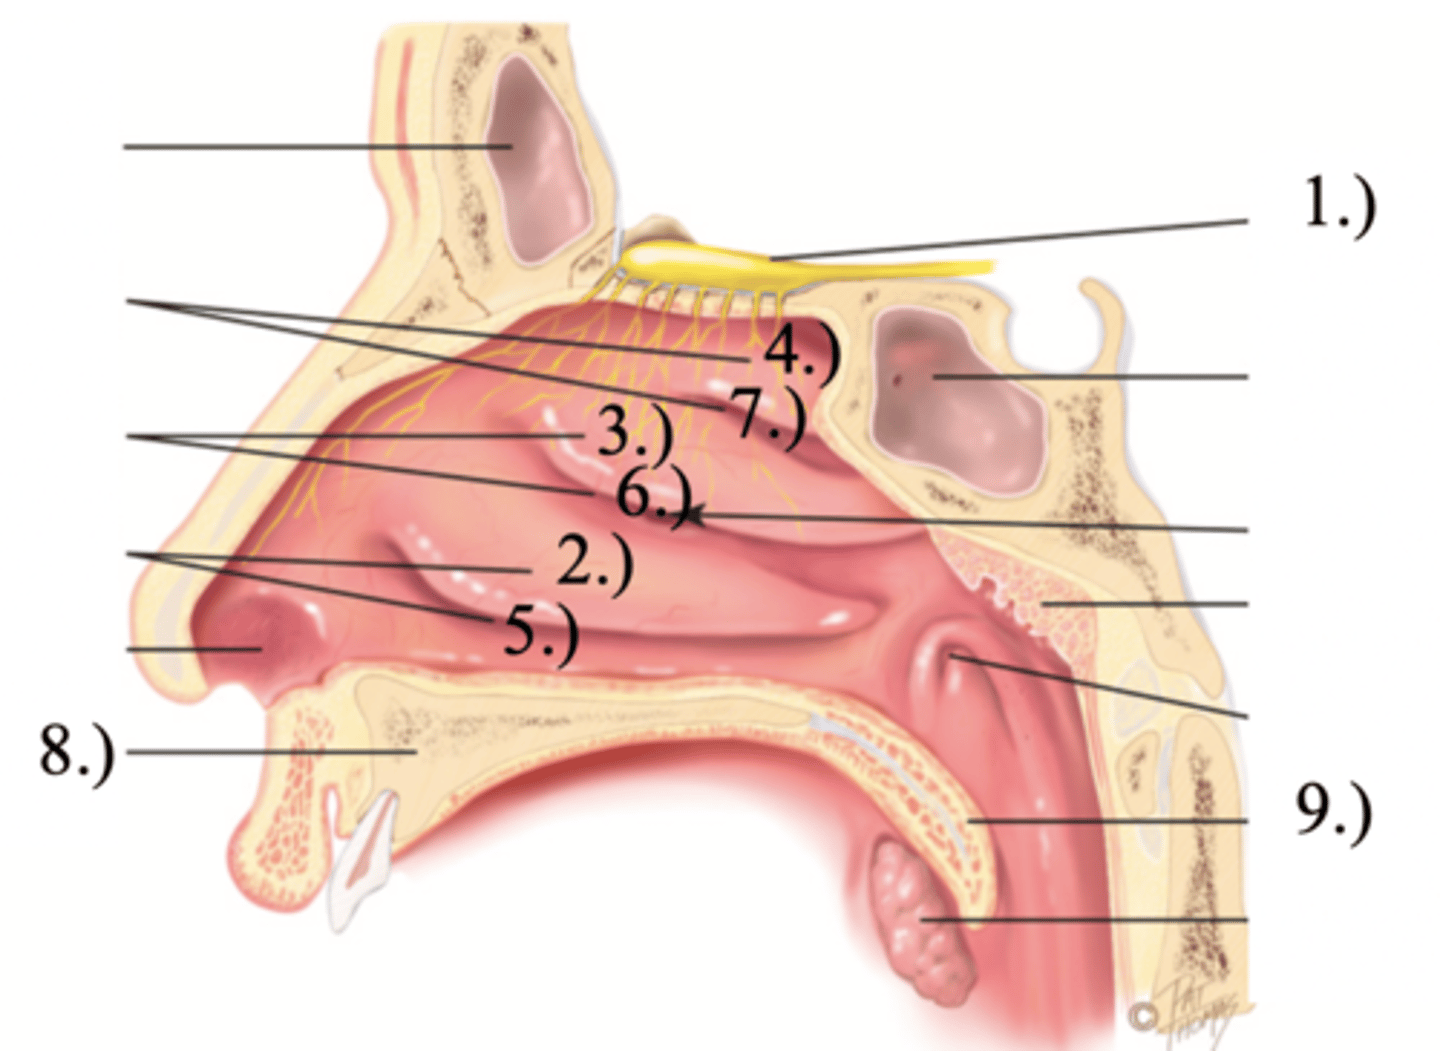

Turbinates (Conchae)

- There's an inferior, middle, and superior one (2.), 3.), 4.))

Olfactory Region

A dime-sized area at the top of each nasal cavity that houses sensors responsible for smell (1.))

Meatuses

- There's an inferior, middle, and superior one

(5.), 6.), 7.))

Anterior palate portion that is supported by the palatine processes of the maxillae and the palatine bones (8.))

Posterior palate portion, not supported by bone (9.))